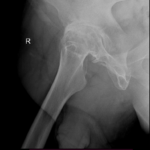

- Osteoarthritis: It is characterized by progressive wearing away of the cartilage of the joint. As the protective cartilage wears down, the bone ends rub against each other and cause pain in the hip. Rheumatoid arthritis: This is an autoimmune disease in which the tissue lining the joint (synovium) becomes inflamed, resulting in the production of excessive joint fluid (synovial fluid). This leads to loss of cartilage causing pain and stiffness.

- Traumatic arthritis: This is a type of arthritis resulting from a hip injury or fracture. Such injuries can damage the cartilage and cause hip pain and stiffness over a period of time.

The most common symptom of hip arthritis is joint pain and stiffness resulting in limited range of motion. Vigorous activity can increase the pain and stiffness which may cause limping while walking.

Diagnosis is made by evaluating medical history, physical examination and X-rays.